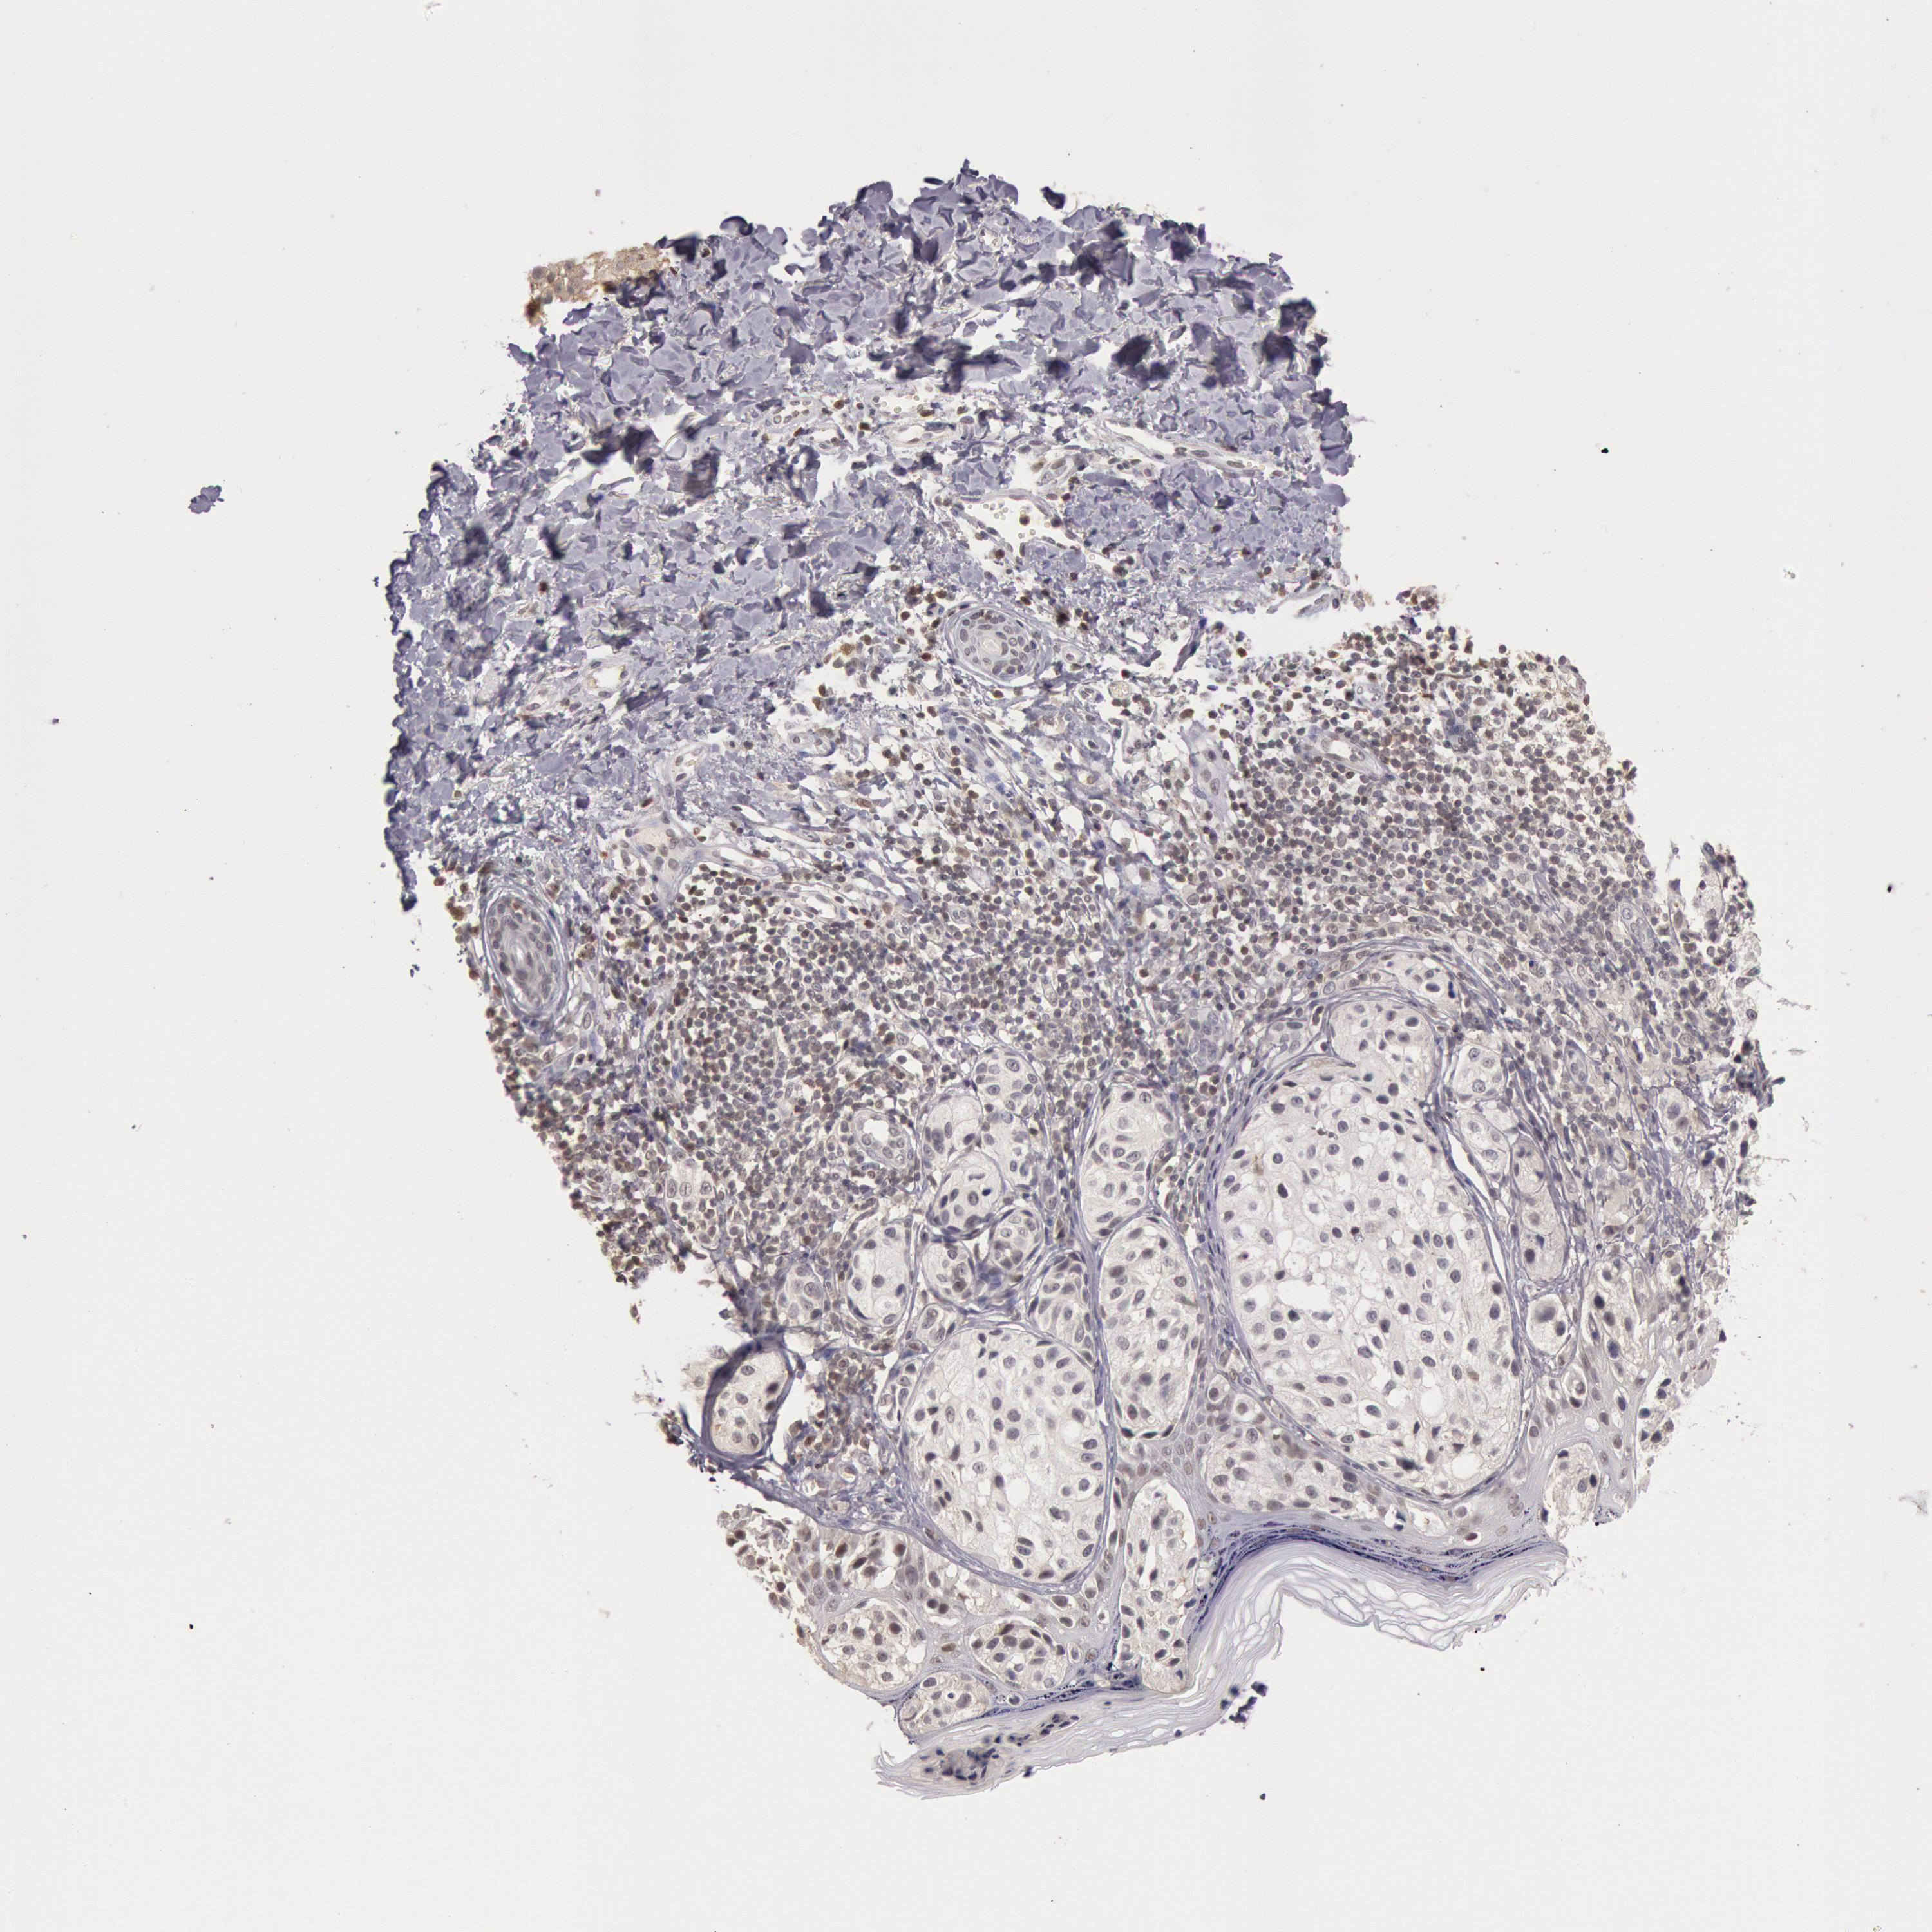

MELANOMA - Protein expressioni

A mouse-over function shows sample information and annotation data. Click on an image to view it in a full screen mode. Samples can be filtered based on level of antibody staining by selecting one or several of the following categories: high, medium, low and not detected. The assay and annotation is described here.

Note that samples used for immunohistochemistry by the Human Protein Atlas do not correspond to samples in the TCGA dataset.

Antibody stainingi

Antibody staining in the annotated cell types in the current human tissue is reported as not detected, low, medium, or high, based on conventional immunohistochemistry profiling in selected tissues. This score is based on the combination of the staining intensity and fraction of stained cells.

Each image is clickable and will lead to virtual microscopy that enables deeper exploration of all samples and also displays staining intensity scores, fraction scores and subcellular localization as well as patient and tissue information for each sample.

Antibody HPA001275

Antibody CAB017442

Staining

High

Medium

Low

Not detected

Intensity

Strong

Moderate

Weak

Negative

Quantity

>75%

75%-25%

<25%

None

Location

Nuclear

Cytoplasmic/membranous

Cytoplasmic/membranous,nuclear

Malignant melanoma, NOS

Malignant melanoma, Metastatic site